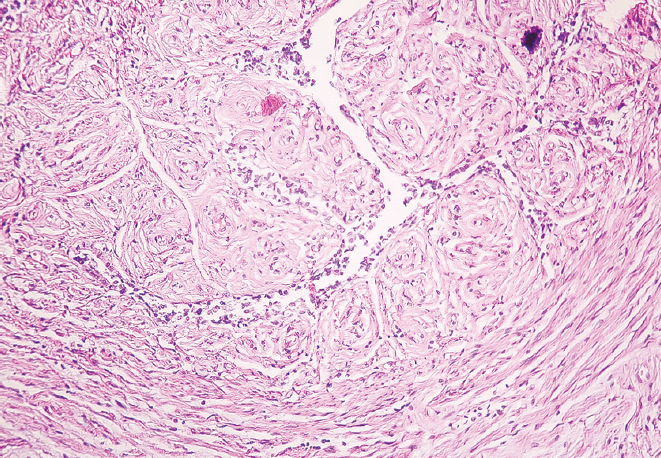

Результаты. Установлено уменьшение показателей наружного диаметра перешейка и воронки обеих маточных труб женщин от молодого возраста к старческому (p < 0,01). В старческом возрасте определено преобладание параметров наружного диаметра перешейка и воронки правой маточной трубы в сравнении с показателями левой маточной трубы (p < 0,01), наряду с этим в молодом возрасте выявлена лишь тенденция к превалированию значений диаметра перешейка и воронки правой маточной трубы (p > 0,05). Гистологическое исследование показало наличие утолщенных складок слизистой оболочки и уплощенного эпителия в исследуемых областях у женщин старческого возраста, истончение слоев мышечной оболочки и разрастание соединительной ткани в сравнении с образцами, взятыми для исследования у женщин молодого возраста.

Заключение. Морфологическая перестройка перешейка и воронки маточных труб от молодого к старческому возрасту заключается в утолщении складок слизистой оболочки, уплощении эпителия, разрастании соединительной ткани в стенке и уменьшении их наружного диаметра с преобладанием параметров в правой маточной трубе.